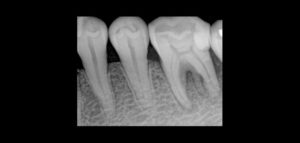

Las imágenes obtenidas mediante CBCT han asumido un papel prominente en el diagnóstico de la disfunción de la articulación temporomandibular (ATM), para la evaluación de